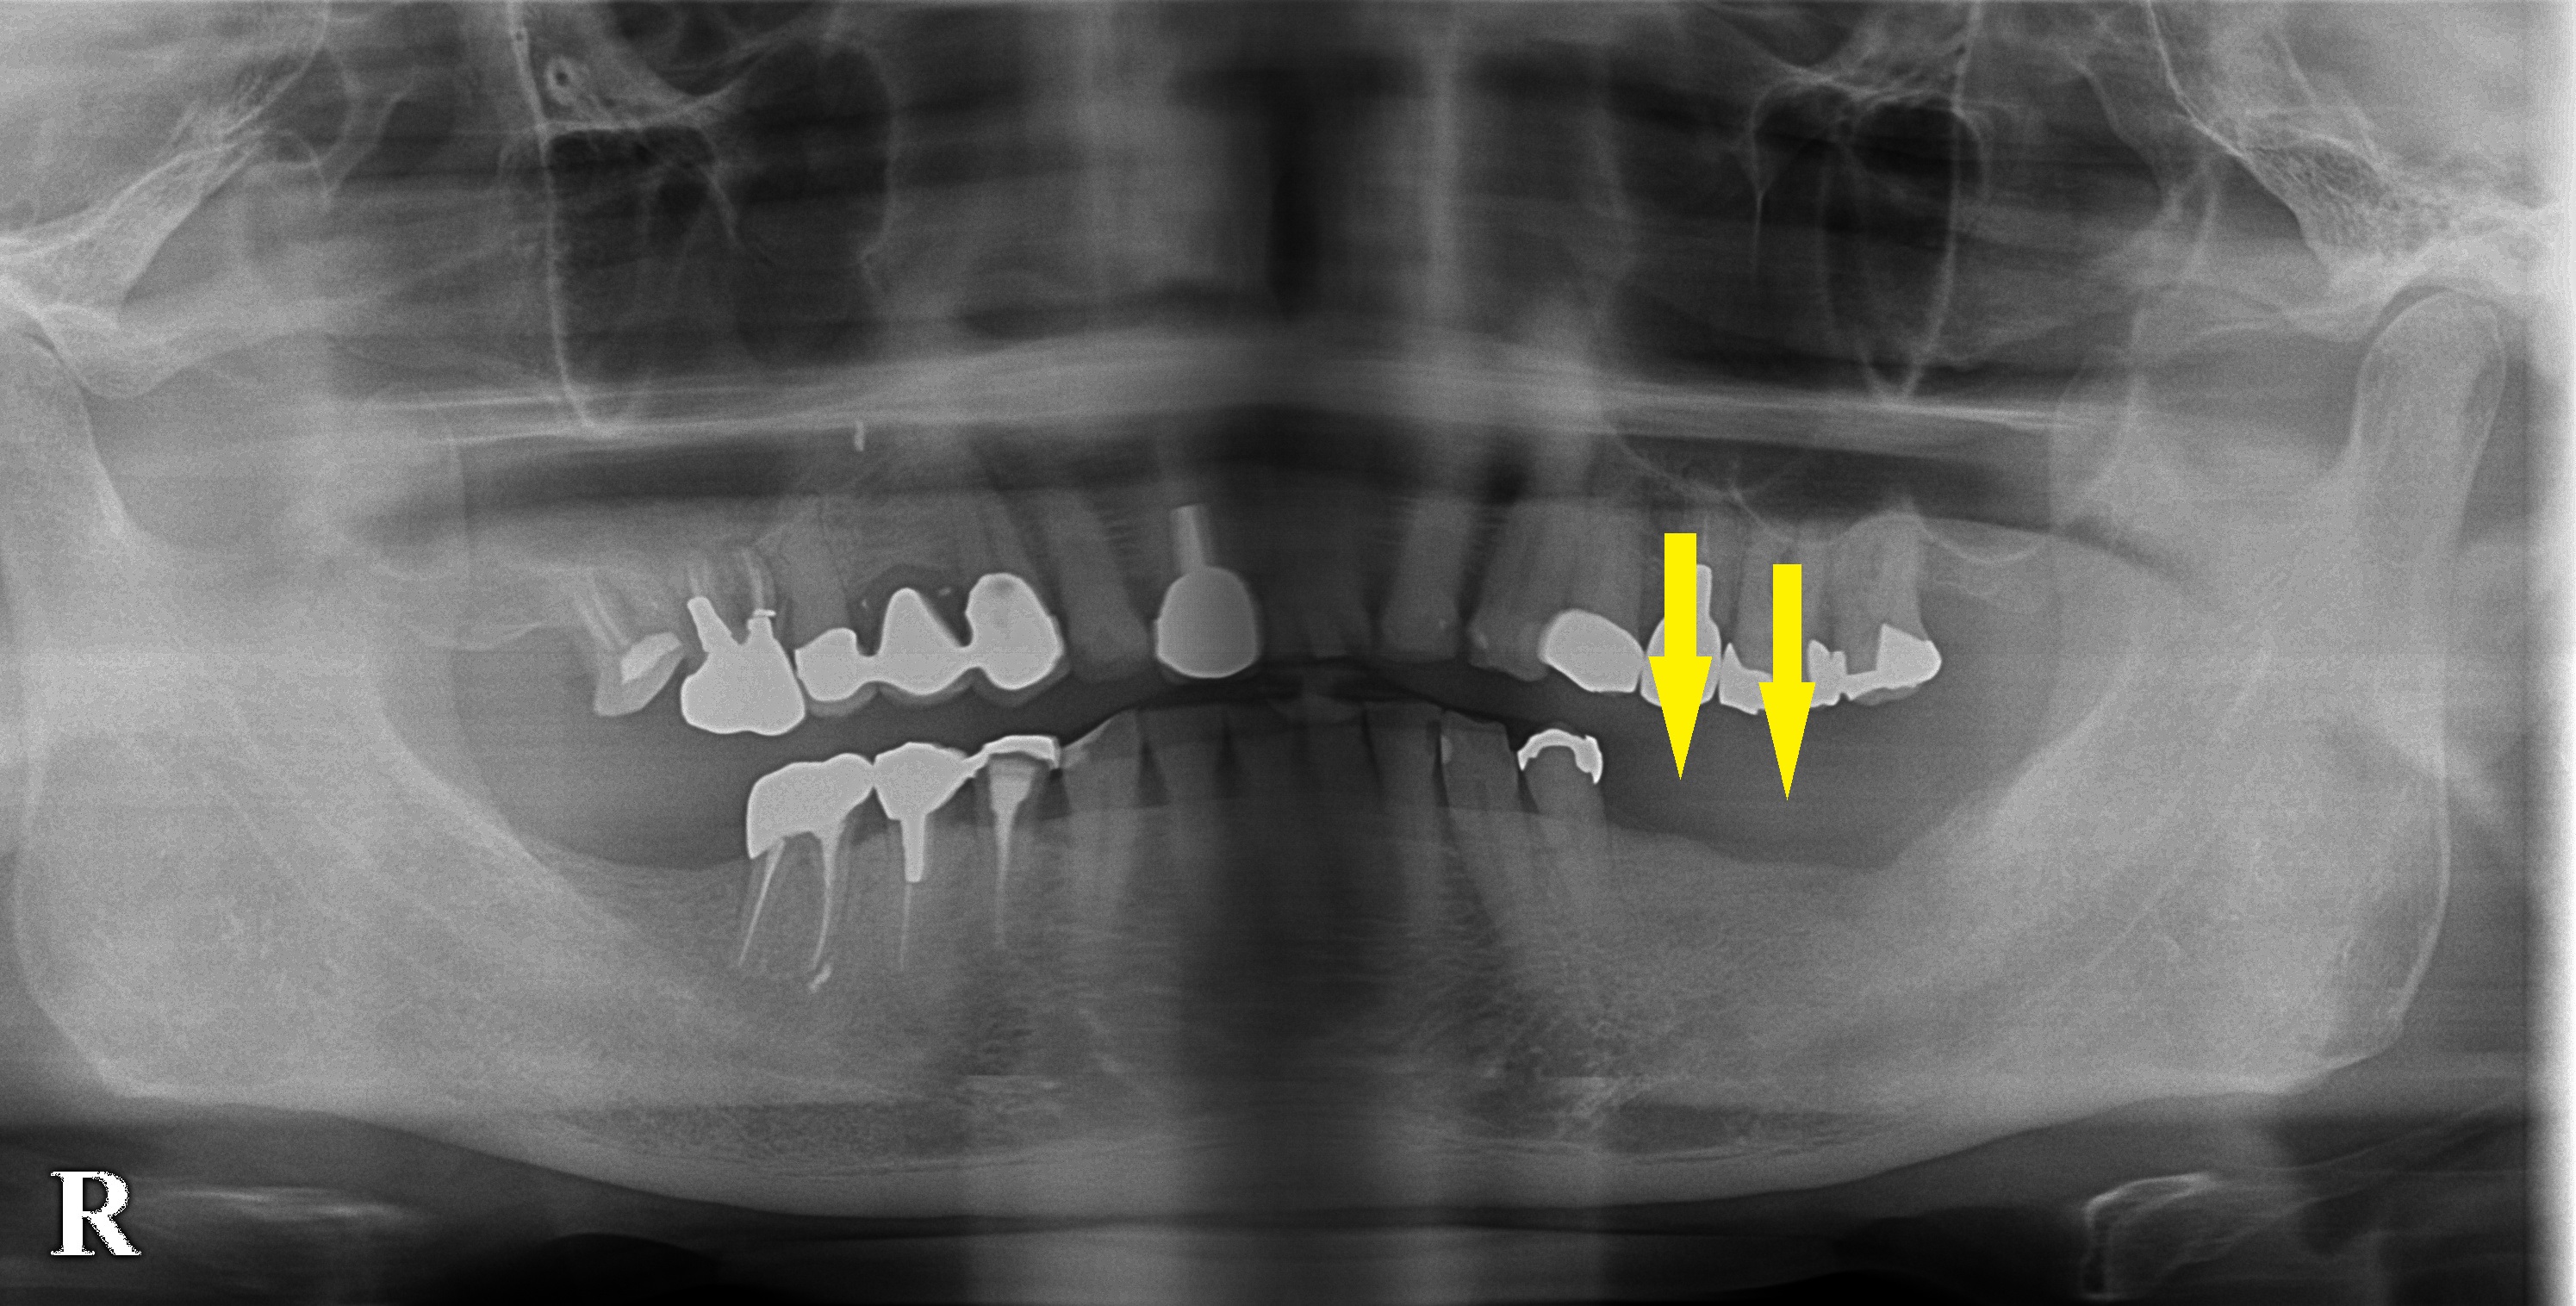

左下顎の臼歯が抜けて、義歯を入れられていたそうですが具合が悪く、インプラント治療を希望されて相談にお出でになりました。

骨の量は問題ないので、臼歯3歯欠損のところに、2本のインプラント埋入を行いました。

ただ、インプラントを長期安定させるための固い歯肉の幅が狭いので、固い歯肉の幅を拡げる手術を追加してから、上部構造を完成させる予定です。